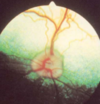

ocular fundus

structures of posterior eye visible on opthalmic exam * optic disc * retina w pigmented epithelium * retinal bvs * choroid inc tapetum - where visible = tapetal fundus (rest = non-tapetal fundus) * sometimes sclera

116

how are dog + cat fundus diff

dogs = white bc nerves becoming myelinated b4 leave eye cats = no myelinated until leave eye => black

117

how is rabbit fundus diff

bvs only medial + lateral + band not circle of myelination

118

how is horse fundus diff

dots of vessels thru choroid layer (= stars of Winslow) * abnormal other species that have large clear retinal bvs from optic disc